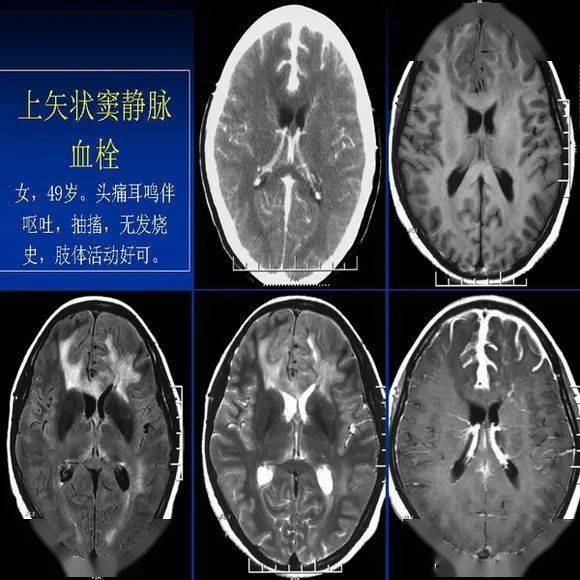

新生儿缺氧缺血性脑病的ct诊断

该课件叙述了婴幼儿脑部mri特点,对新生儿缺血缺氧性脑病的影像学表现